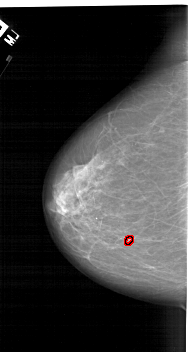

A_1124_1.RIGHT_CC

RIGHT_CC LINES 6571 PIXELS_PER_LINE 3571 BITS_PER_PIXEL 12 RESOLUTION 43.5 NON_OVERLAY

FILE: A_1124_1.LEFT_CC.OVERLAY

TOTAL_ABNORMALITIES 1

ABNORMALITY 1

LESION_TYPE CALCIFICATION TYPE PLEOMORPHIC DISTRIBUTION LINEAR

ASSESSMENT 4

SUBTLETY 1

PATHOLOGY MALIGNANT

TOTAL_OUTLINES 1